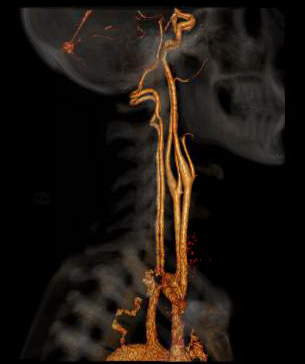

CTA of the Head and Neck image A for Radiology

How it works: CT angiography (CTA) evaluates the major vessels of the head, neck or both. An iodine based contrast agent is rapidly injected through an IV placed in a vein, usually in the arm. A CT scan uses x-rays to acquired images as the contrast bolus passes through the arteries. The data can then be reviewed in multiple planes, and 3 dimensional images can also be created for review.

Equipment: Most commonly, a 64 channel Philips CT scanner is used, however, in some situations a 16 or 256 channel CT scanner may be used. OHSU is an ACR accredited CT facility.

Benefits: CT angiography is a fast and minimally invasive method of evaluating vessels for abnormalities such as narrowing, blockage, aneurysms, and other vascular malformations.

CTA of the Head and Neck image B for Radiology

Exam Preparation: The technologist will interview you prior to the scan to make sure you do not have contraindications to the injection of intravenous contrast, such as contrast allergy or kidney problems.  If you have had an allergy to iodine based contrast in the past, you should discuss this with your physician before the study. In some situations, an alternative imaging method may be considered, or you may receive medication that needs to be taken before the study to reduce your risk of reaction. In some situations, kidney function labs may also be checked before your study. An IV will be placed, usually in the arm.

CTA of the Head and Neck image C for Radiology

Adverse reactions to contrast materials are uncommon, but can range from mild to severe.  Severe reactions are very uncommon. Further information about the risks and benefits of x-rays and contrast material can be found here.

Content by Dr. Louis P. Riccelli